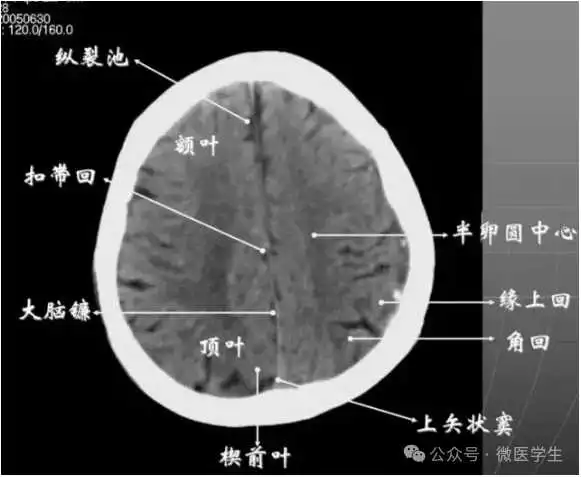

九面:听眦蝶鞍三下上体顶卵园灰质象1.听眦线层面(00mm)2.蝶鞍层面(+10mm)3.鞍上池层面(+20mm)4.三脑室下部层面(+30mm)5.三脑室上部层面(+40mm)6.侧脑室体部层面(+50mm)7.侧脑室顶部层面(+60mm)8.半卵圆中心层面(+70mm)9.灰质层面(+80mm)

在胼胝体和侧脑室上方,大脑镰自前向后贯穿中线。白质部分为半卵圆中心,额叶范围缩小,顶叶所占比例扩大,枕叶基本消失。

- 半卵圆中心:位于胼胝体上方,由左右大脑半球髓质形成的有髓纤维,对称位于大脑镰两侧区域。

已近颅顶,大脑镰清晰可见,其旁的脑灰质和脑沟十分清楚。顶叶较小,额叶较小。

- 放射冠:是内囊到大脑皮质间的放射状纤维白质。